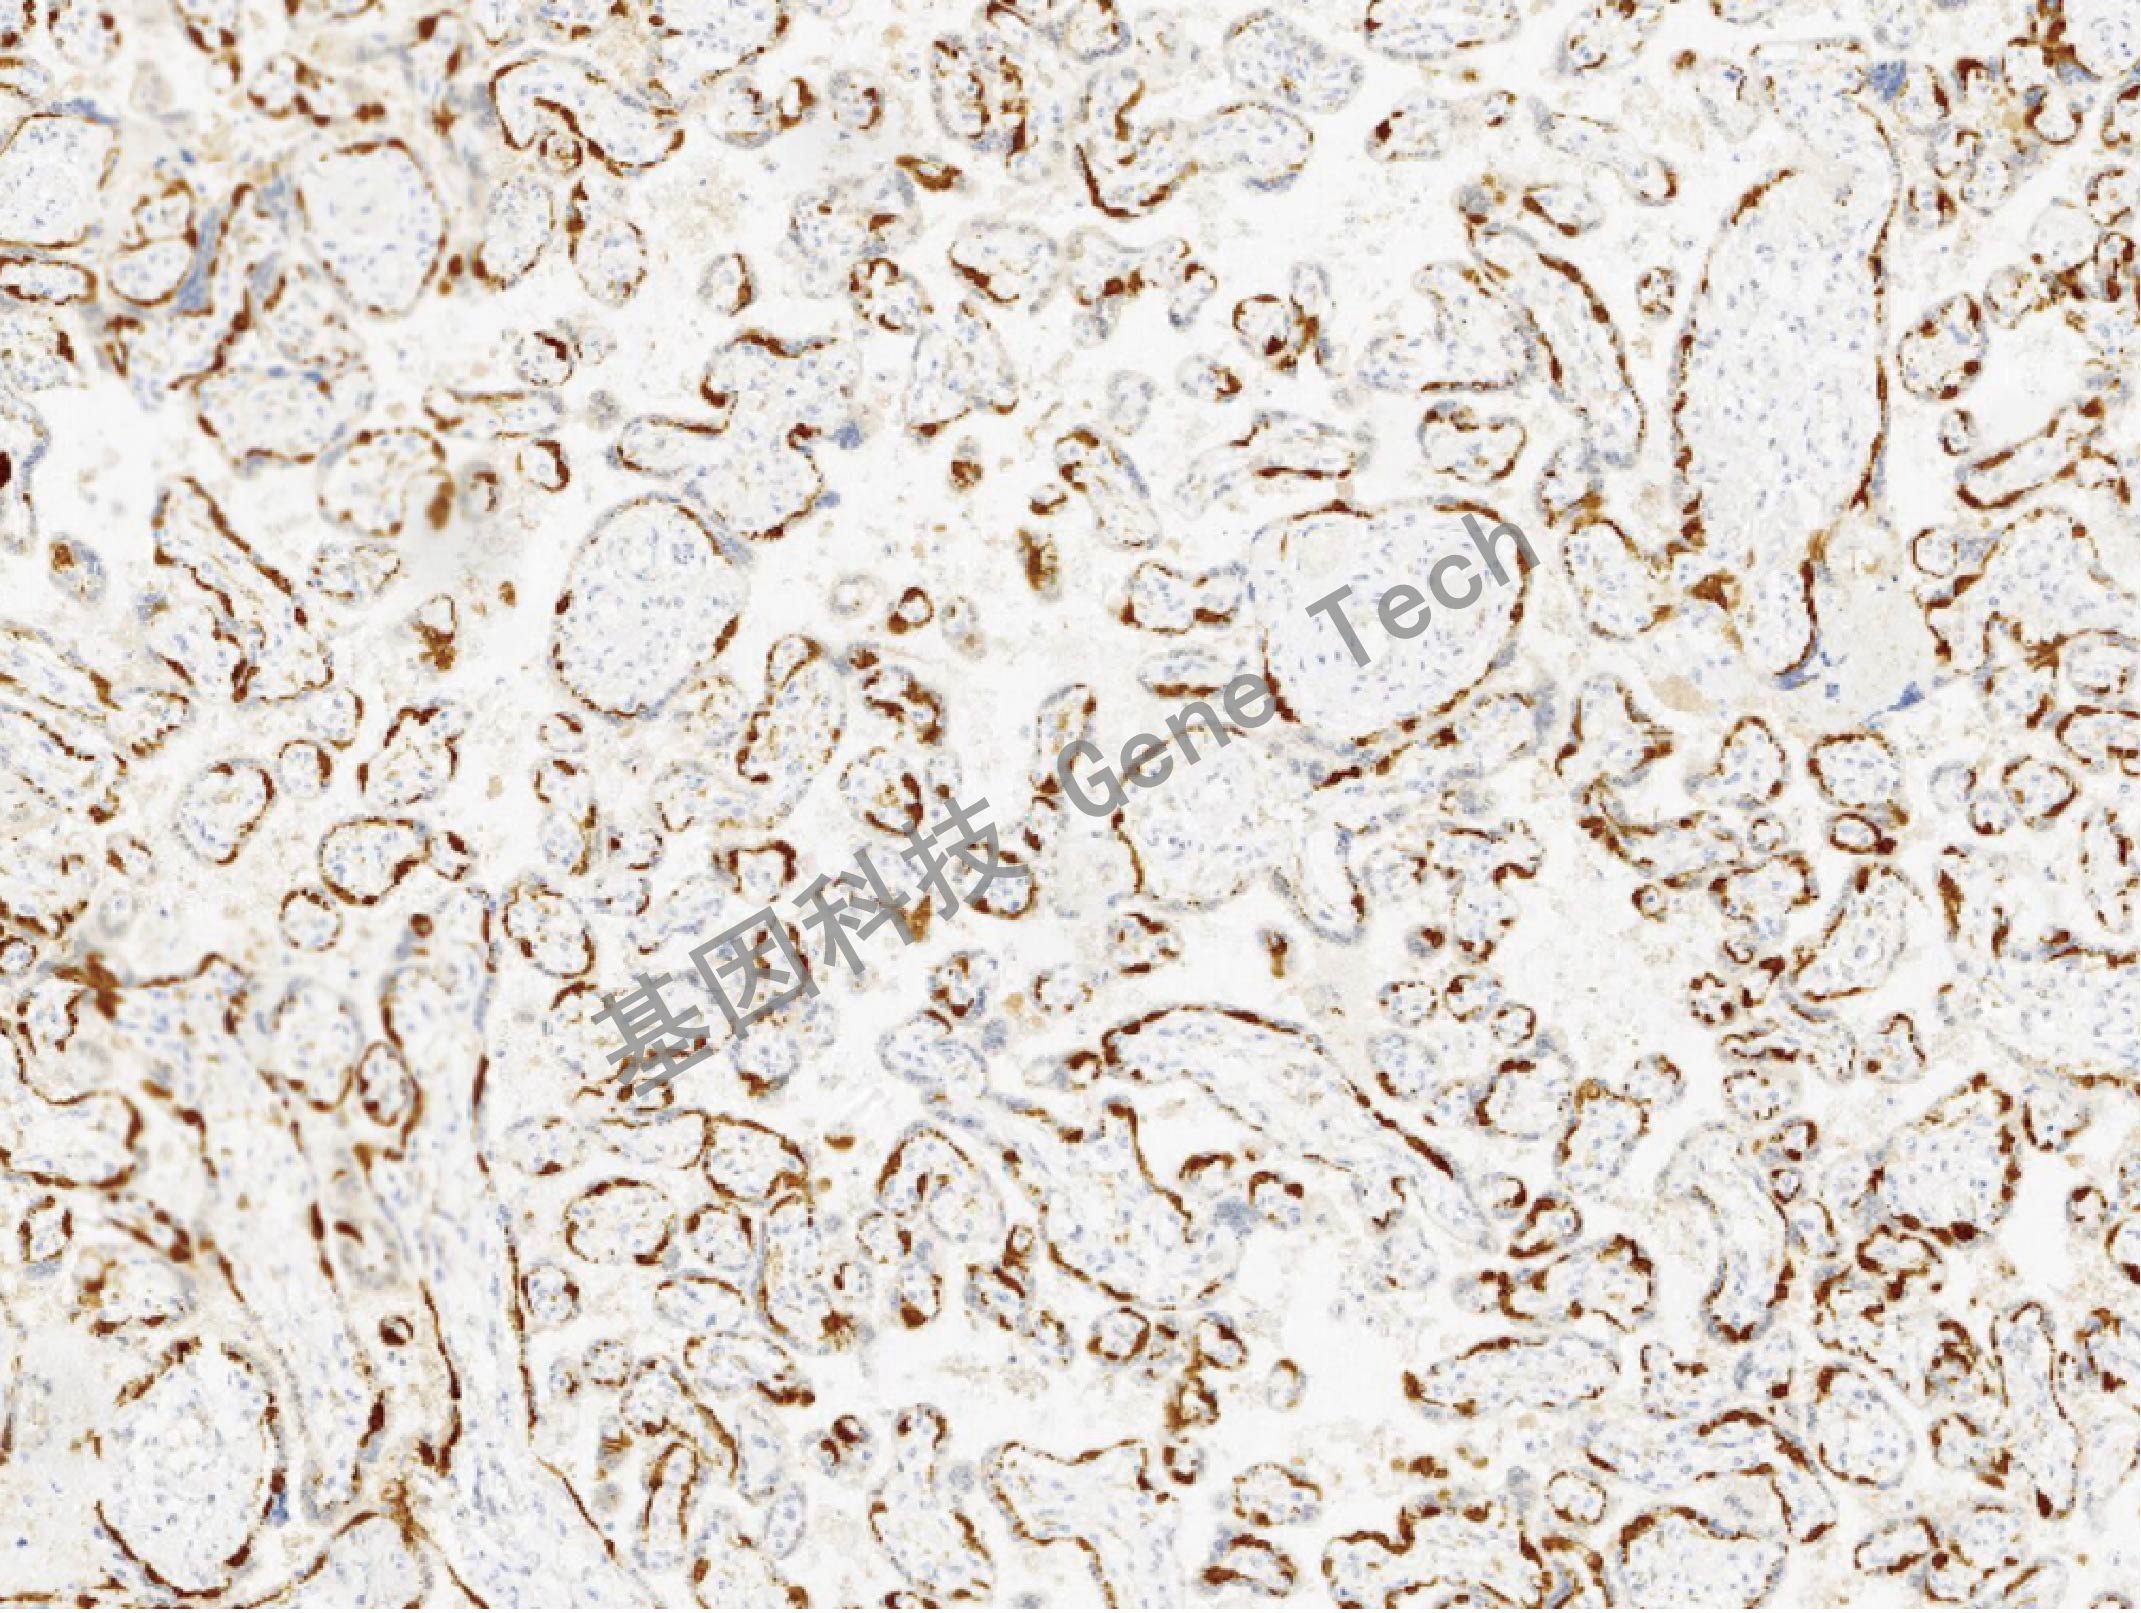

| 預(yù)處理:高pH熱修復(fù) | 陽(yáng)性部位:細(xì)胞漿 | 陽(yáng)性對(duì)照:胎盤 |

| 胎盤石蠟切片,用 PEG10(GT2418)染色,細(xì)胞漿陽(yáng)性,DAB 顯色。 | ||